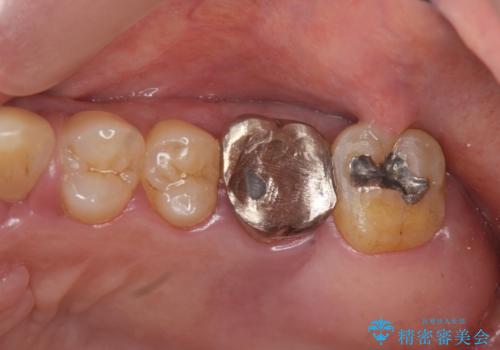

歯周病に対する全体治療

- 近医で「重度の歯周病です、入れ歯にする必要がある。」、と言われ入れ歯以外の方法がないか相談にみえられました。

再生治療、歯周外科を行うことで歯周病治療を行い、残すことのできる歯の歯周環境を整える。

残すことのできない歯は抜去したのち骨造成を含めたインプラント治療を行い、しっかりとした咬合関係を確立していきます。

治療期間はかかりましたが、しっかりと歯周病治療・インプラント治療を行ったおかげで歯周病の状態は非常に良くなり、安定した咬合関係を確立することができました。